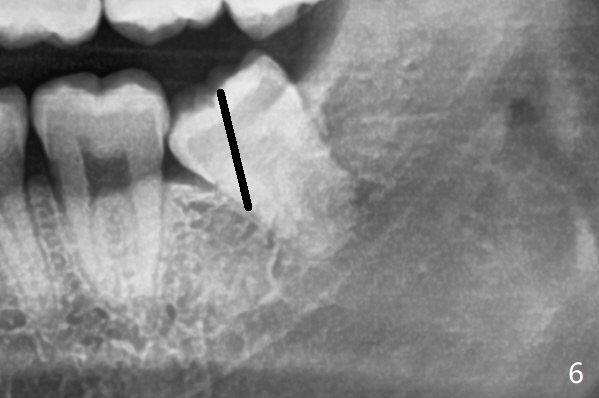

下牙槽神经管(*)位于智齿根尖下方(图一);而没有颊侧沟形成,也没有大量松动智齿,包括牙根,直接切割牙(图六:黑线)